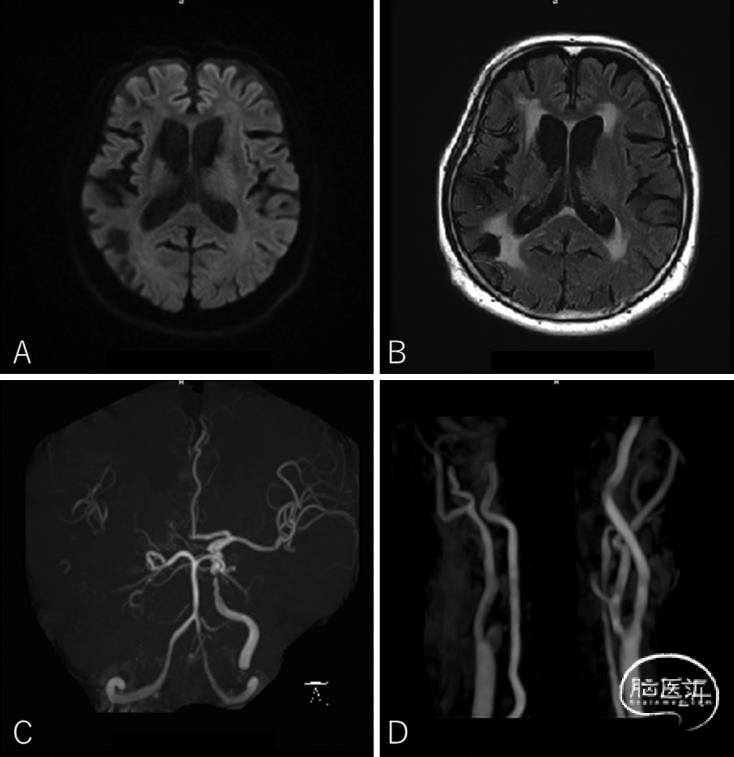

● 格拉斯哥昏迷评分(GCS)为15分(E4V5M6),出现症状时降至9分。MRI显示右侧颈内动脉(ICA)慢性闭塞,左侧ICA起始部狭窄(NASCET标准29%),左侧ICA C3段狭窄(图1)。头颅CT和MRI均未发现脑梗死病灶。

图1:术前MRI检查